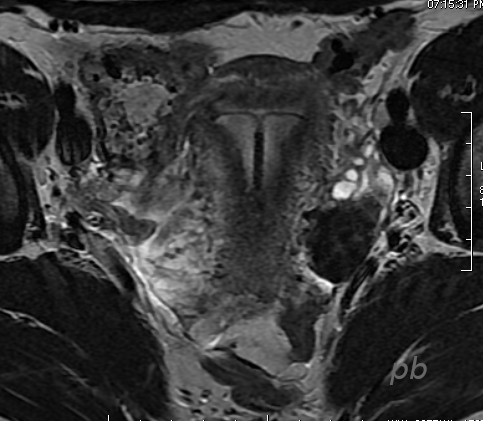

11 – DIU en IRM

Coupe axiale T2.

Les DIU (cuivre et hormonaux) en IRM apparaissent en hyposignal en T1 comme en T2.

11 – IUD on MRI

Axial T2-weighted image.

IUDs (both copper and hormonal) appear as hypointense (low signal) on both T1 and T2 MRI sequences.